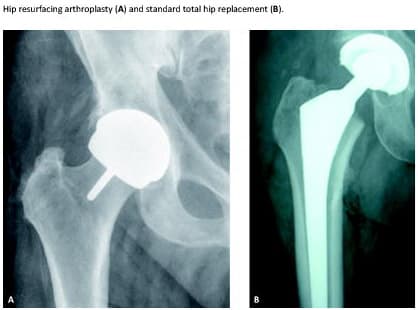

Introduction: The purpose of this study was to investigate patient-reported outcome in terms of satisfaction in two study groups that had undergone hip resurfacing arthroplasty (HRA) or total hip replacement (THR). The procedure consists of placing a hollow, mushroom-shaped metal cap over the femoral head while a matching metal cup is placed in the acetabulum (pelvis socket).

During the past decade, hip resurfacing arthroplasty (HRA) has been used in selected Danish patients with degenerative hip disease [1]. HRA is used mainly in cases where younger patients might otherwise be expected to replace their standard prosthesis within 10-15 years. The procedure consists of placing a hollow, mushroom-shaped metal cap over the femoral head while a matching metal cup is placed in the acetabulum (pelvis socket). HRA may have some advantages compared with conventional total hip replacement (THR). Resurfacing surgery preserves more femoral bone than conventional THR surgery which preserves the option of further treatment via a standard THR. Register studies show an overall increased failure rate of HRA compared with THR, but in male patients younger than 65 years with primary osteoarthritis, the survival rates of HRA are equivalent to those of THR [2, 3]. The internationally recommend age group for HRA prosthesis is younger patients [4].